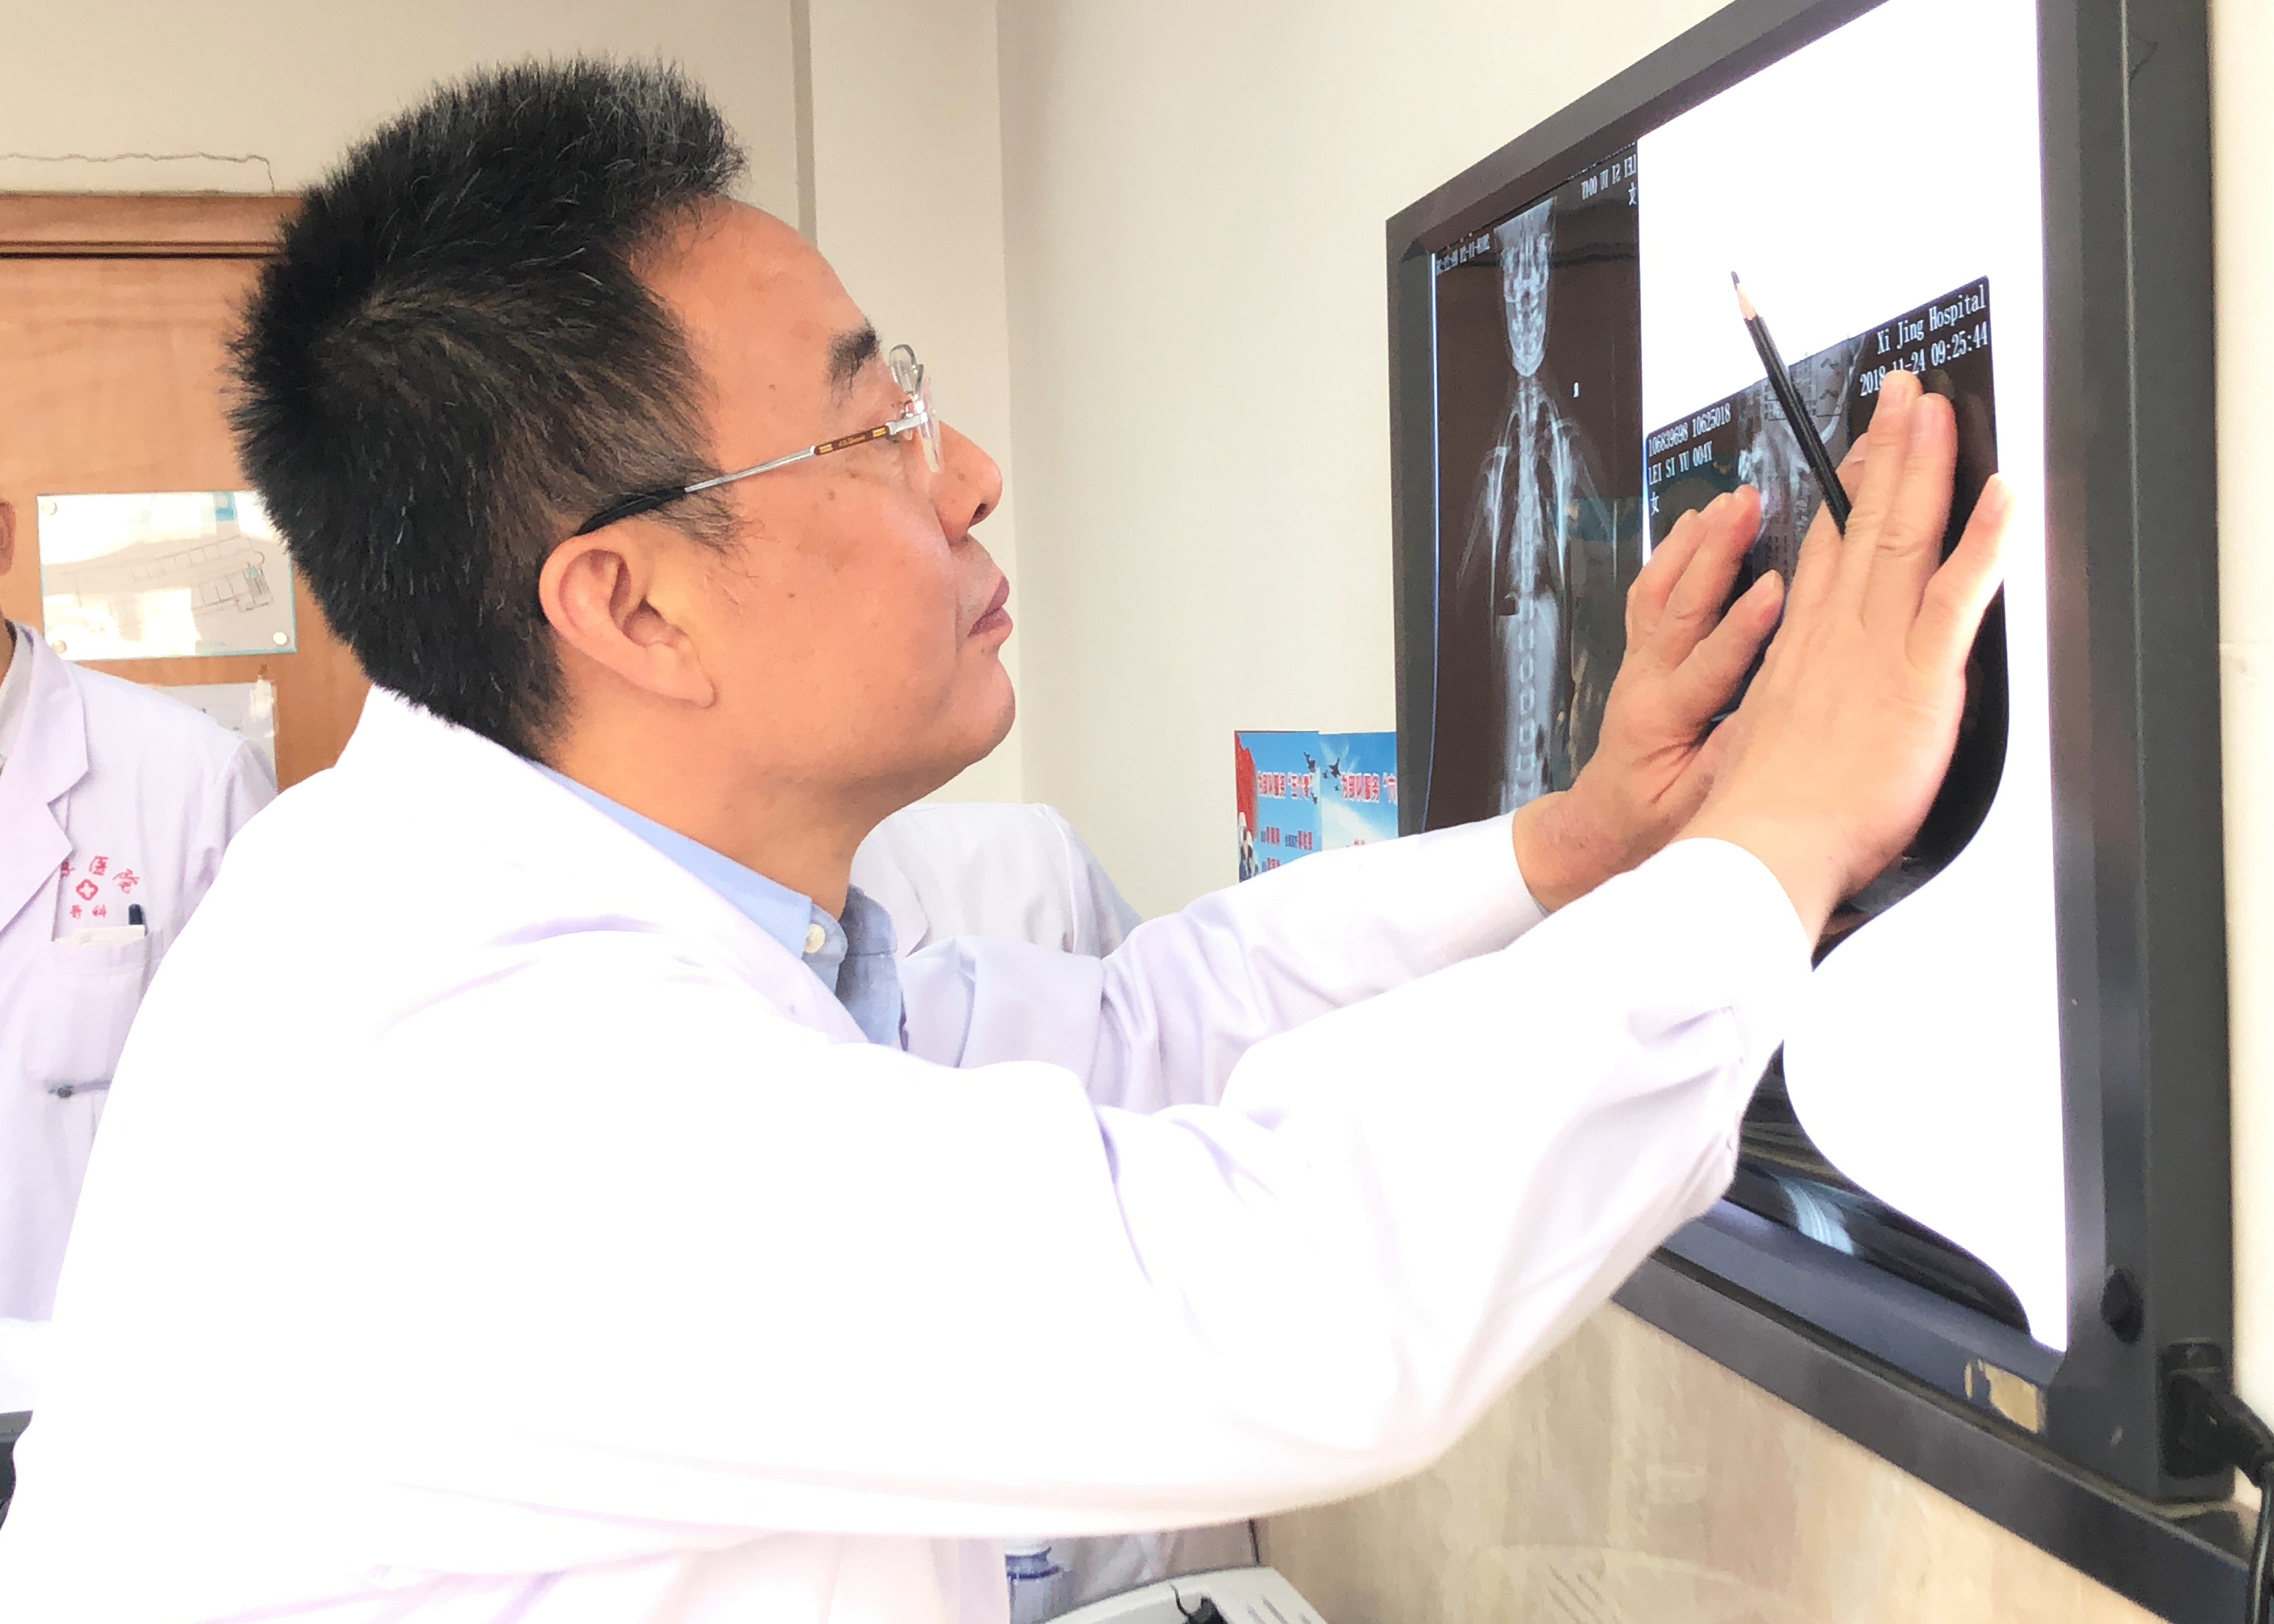

由于六月为儿童脊柱侧弯进行的免费治疗活动,近期接诊很多年龄非常小的脊柱侧弯患儿,对于这种早发性脊柱侧弯,我们会有一种针对性的治疗方式——生长棒治疗。

什么是生长棒治疗呢?

目前,国内外脊柱矫形外科医生已经达成共识,对于严重的、进展性的早发性脊柱侧凸畸形,如保守治疗效果不佳,需早期进行外科干预。外科干预主要分为融合技术以及非融合技术两大类,其各有优缺点。

首先是矫形支具矫正的保守方法,试图矫正部分畸形或控制畸形的发展速度,待年龄大了以后在进行矫正固定融合手术;但是往往由于幼儿年龄较小而无法配合切实佩带支具,或者是畸形发展速度较快而支具无法控制,生长棒既矫正畸形又不影响儿童的生长发育,适用于年龄小、骨骼发育潜力大的患儿。